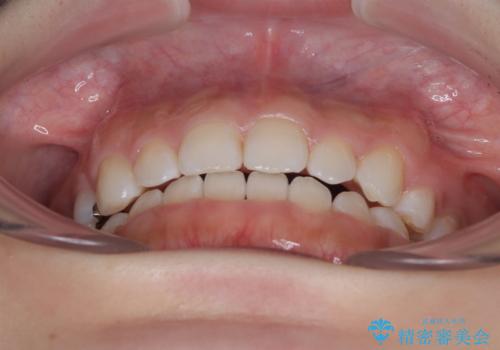

- 前歯のクロスバイトと口元の膨らんだ横顔の印象を気にして来院された患者様です。

レントゲン写真の分析結果からは、それほど口元が突出しているという結果にはなりませんでした。

しかしながら、唇を閉じたときに口元に緊張感があり、そのまま叢生を解消すると横顔が突出した印象になる可能性が高かったため、上下左右の小臼歯4本を抜歯して、ワイヤー装置にて矯正治療を行うこととしました。